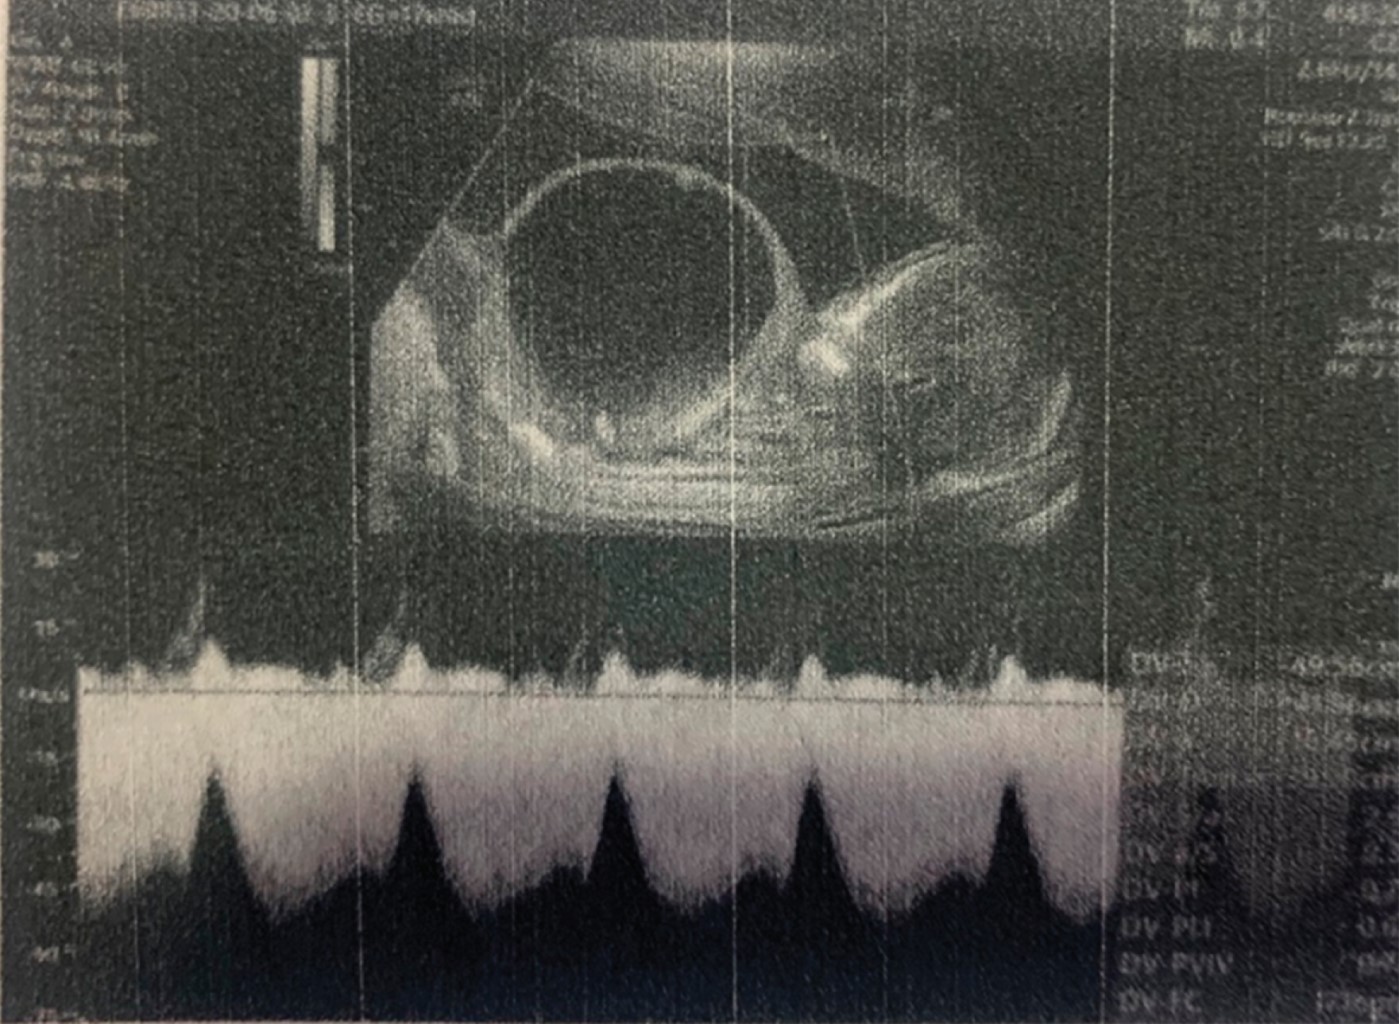

Paciente primigesta de 29 años, con hipotiroidismo controlado como único antecedente médico de importancia. Refiere haber recibido adecuado control prenatal, con ingesta de multivitamínicos, ácido fólico y ácido acetilsalicílico 100 mg desde inicios tempranos de la gestación. Asimismo, se diagnosticó diabetes gestacional a las 25 semanas de gestación, la cual se manejó con tratamiento nutricional. Se le realiza ultrasonido a las 12.5 semanas de gestación de primer trimestre reportando tamaño vesical de 9.4 mm (arriba de lo esperado) (Figura 1), con dilatación pielocalicial en ambos riñones. A las 16 semanas de gestación acude a control donde se diagnostica obstrucción urinaria baja con megavejiga fetal de 5.7 × 5.8 × 5.2 cm (Figura 2), motivo por el cual se envía a cirugía fetal para tratamiento. Se realiza amniocentesis con reporte de cariotipo 46 XY, sin anormalidades numéricas ni estructurales.

A las 17.5 semanas de gestación se realiza ablación láser transvesical de valvas uretrales posteriores sin complicaciones. Posteriormente se observa en ultrasonidos de seguimiento, disminución del tamaño vesical con función renal conservada y líquido amniótico dentro de parámetros normales para edad gestacional.

Figura 1